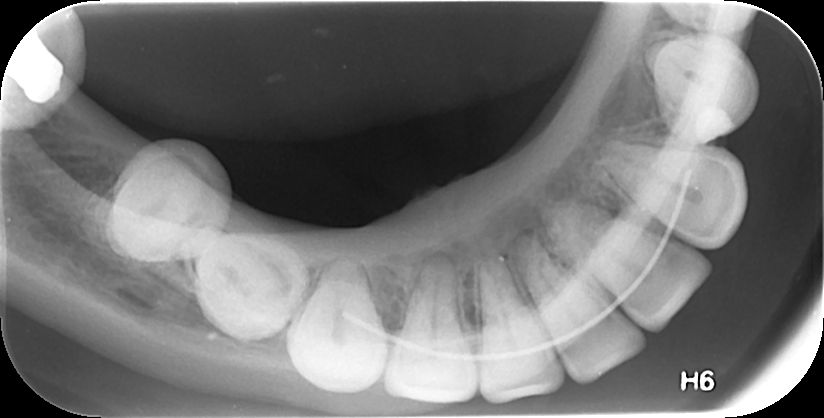

3. ΟΠΙΣΘΟΜΥΛΙΚΗ ΑΚΤΙΝΟΓΡΑΦΙΑ

Με την οπισθομυλική ακτινογραφία επιτυγχάνεται η ταυτόχρονη απεικόνιση των μυλών των άνω και κάτω οπισθίων δοντιών ενός ημιμορίου (μιας πλευράς) με μία λήψη. Λαμβάνεται με την τοποθέτηση του ακτινογραφικού πλακιδίου εσωτερικά των δοντιών (προς την πλευρά της γλώσσας και του ουρανίσκου) και παράλληλα με αυτά. Χρησιμοποιείται ειδικός συγκρατητήρας οπισθομυλικών, τον οποίο δαγκώνει ο εξεταζόμενος.

Χρησιμοποιείται για την ανίχνευση τερηδόνων στις μύλες των δοντιών, κυρίως στις όμορες επιφάνειές τους (γειτνιάζουσες επιφάνειες δοντιών).

Η λήψη της είναι γρήγορη (διαρκεί λίγα δευτερόλεπτα) και ανώδυνη.